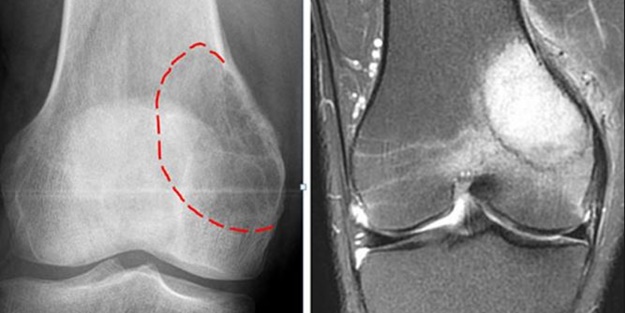

Hafif bir ağrıdan ağır bir ağrıya kadar değişen kemik ağrıları kemik kanseri hastalarının ortak şikâyetidir. Kanser büyüdükçe şikayetlerinizde büyüyecektir ve muhtemelen yürüyüş veya kaldırma gibi ortak hareketlerinizi de engelleyecektir.